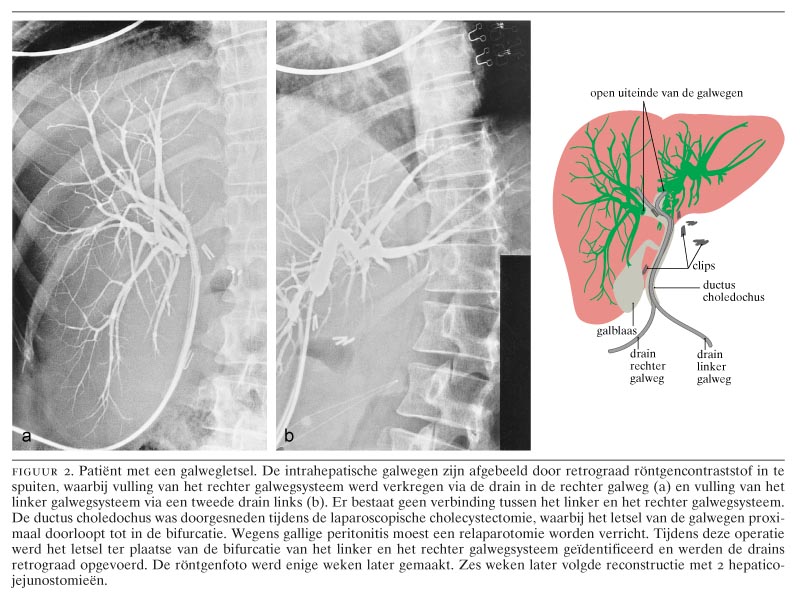

Galwegletsel na laparoscopische cholecystectomie Nederlands Tijdschrift voor Geneeskunde